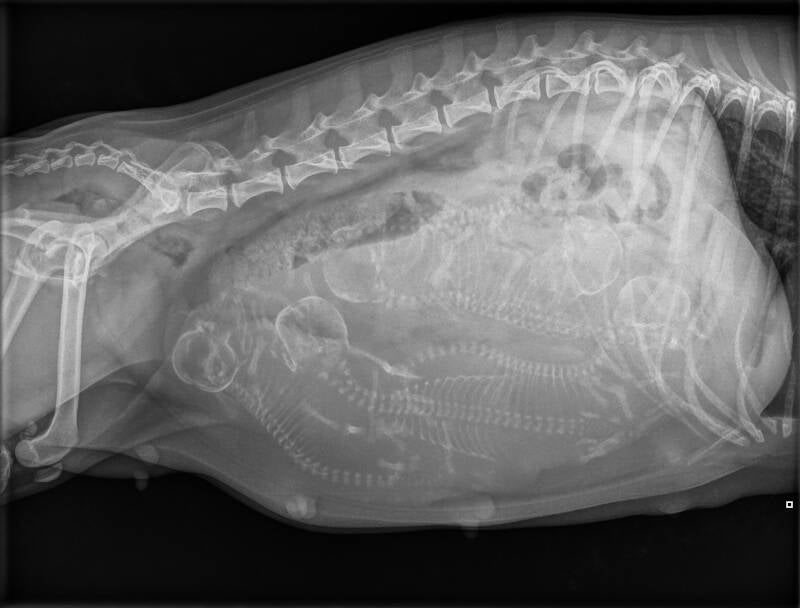

De röntgenfoto ontvangen van Macy. 5 mooie lijfjes te zien. We kunnen ons nu goed gaan voorbereiden. Het gaat niet lang meer duren.

Vandaag de röntgen foto gemaakt van Divani der buik. We hebben er zeker 7 kunnen tellen en ik zelf twijfel zelfs nog over een nr 8.